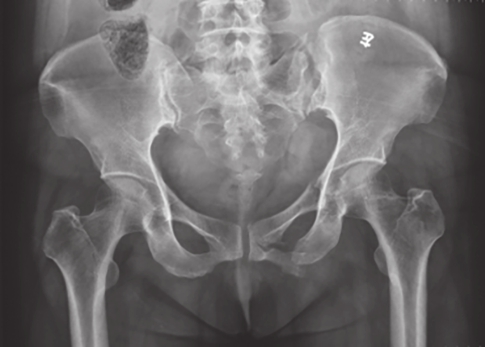

最为常用,患者仰卧,射线呈前后方向垂直投射,骨盆入口边缘与躯干纵轴呈45°~60°夹角。该位像基本能了解骨盆前后环骨折及骶髂关节骨折脱位情况。可用于鉴别骶骨、骨盆髋臼、近端股骨等部位骨折(图2-1)。

图2-1 骨盆前后位X线片

可见左侧骶髂关节骶骨及髂骨面局部骨质断裂,关节间隙增宽,左侧耻上、下支骨折,累及耻骨联合左侧缘。